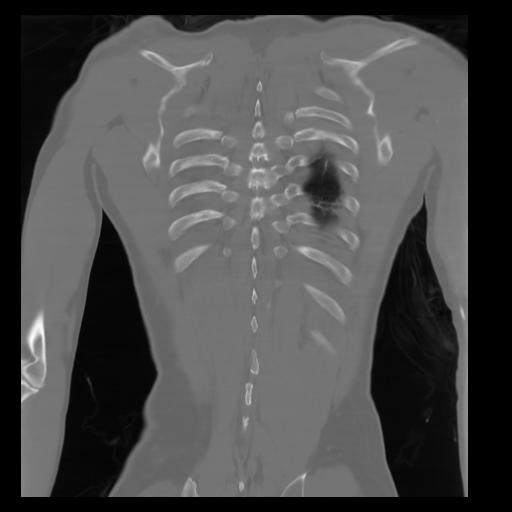

29 CUERPO,CE,Coronal,3.000,CUERPO,Coronal,